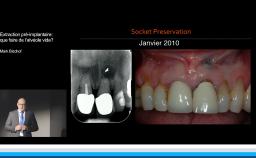

Edentement au secteur anterieur: le défi pour une esthetique optimale

A partir de la description des facteurs de risque esthétique du bloc incisivo-canin maxillaire, de la présence d’os et de gencive autour des implants, le conférencier présente une succession de cas cliniques décrivant ses procédures chirurgicales et prothétiques.